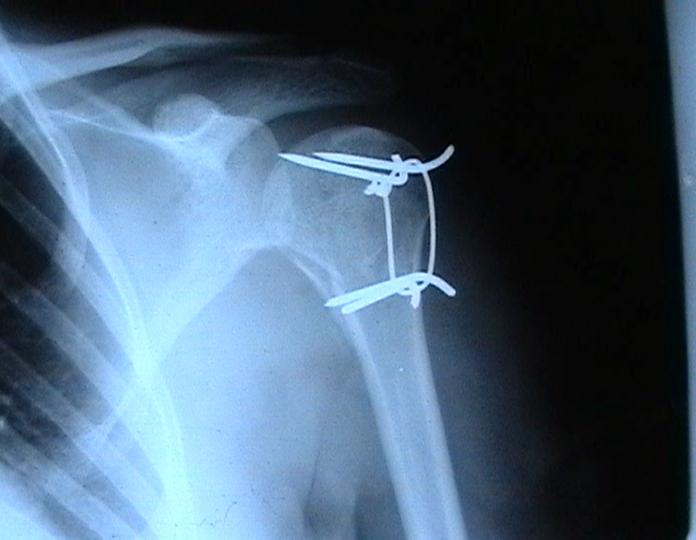

Переломовывих плеча сложная проблема и технически не уверен как для коллег, но для меня сколько я не встречался, технически сложно *вытянуть* вывихнутую головку из-под впадины. Последнее время не применяю пластины для фиксации перелома, а использую спицы и проволочную петлю (тем более часто и густо спонгиозные винты не держатся в головке прочно).